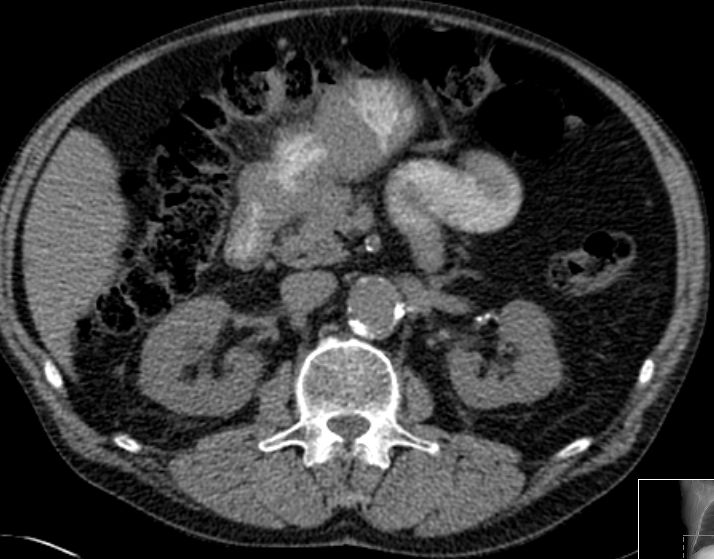

aortaler Bulk |

80-jähriger Mann mit einem retroperitonealen NHL.![]() |

Paraaortale LK |

Befall der Nl. paraaortales links![]() | |||